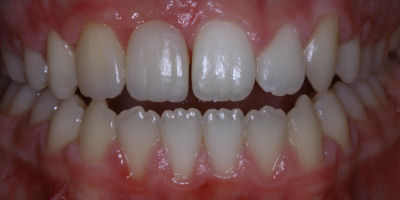

Before/After

Repair Worn Teeth